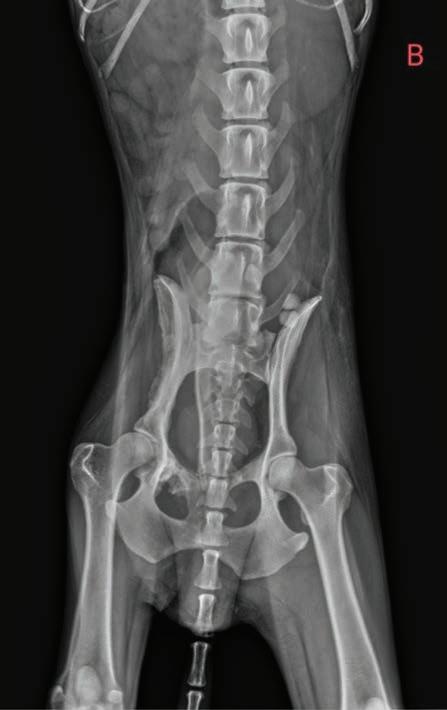

Se realizaron radiografías torácicas y en la proyección lateral derecha se observó, craneal a la silueta cardiaca, una opacidad tejido blando mal definida que producía efecto silueta positivo con esta. La tráquea se visualizó desplazada dorsalmente y el atrio izquierdo aumentado de tamaño. El parénquima pulmonar mostraba un aumento de opacidad en su área caudodorsal, compatible con un patrón pulmonar intersticial no estructurado difuso, el cual se consideró normal debido a que la radiografía fue tomada en fase espiratoria inicial

163

y a la condición corporal del paciente. En la proyección ventrodorsal, el mediastino craneal se observó en el límite superior de tamaño, presentándose un tamaño dos veces superior a la anchura de la vértebra torácica (Fig. 1). Este cambio es compatible con una imagen artefactual secundaria a la leve rotación que presenta la radiografía y a la condición corporal del paciente. El diagnóstico radiológico más probable fue una masa mediastínica craneoventral y cardiomegalia izquierda. En la ecocardiografía transtorácica se confirmó el diagnóstico de enfermedad degenerativa de la válvula

Figura 1. Radiografías torácicas en proyección lateral derecha (A) y ventrodorsal (B) donde se visualiza el área de opacidad de tejido blando craneal a la silueta cardíaca (flechas blancas). En la proyección ventrodorsal se visualiza el mediastino craneal que se presenta en el límite superior de grosor (flechas rojas).